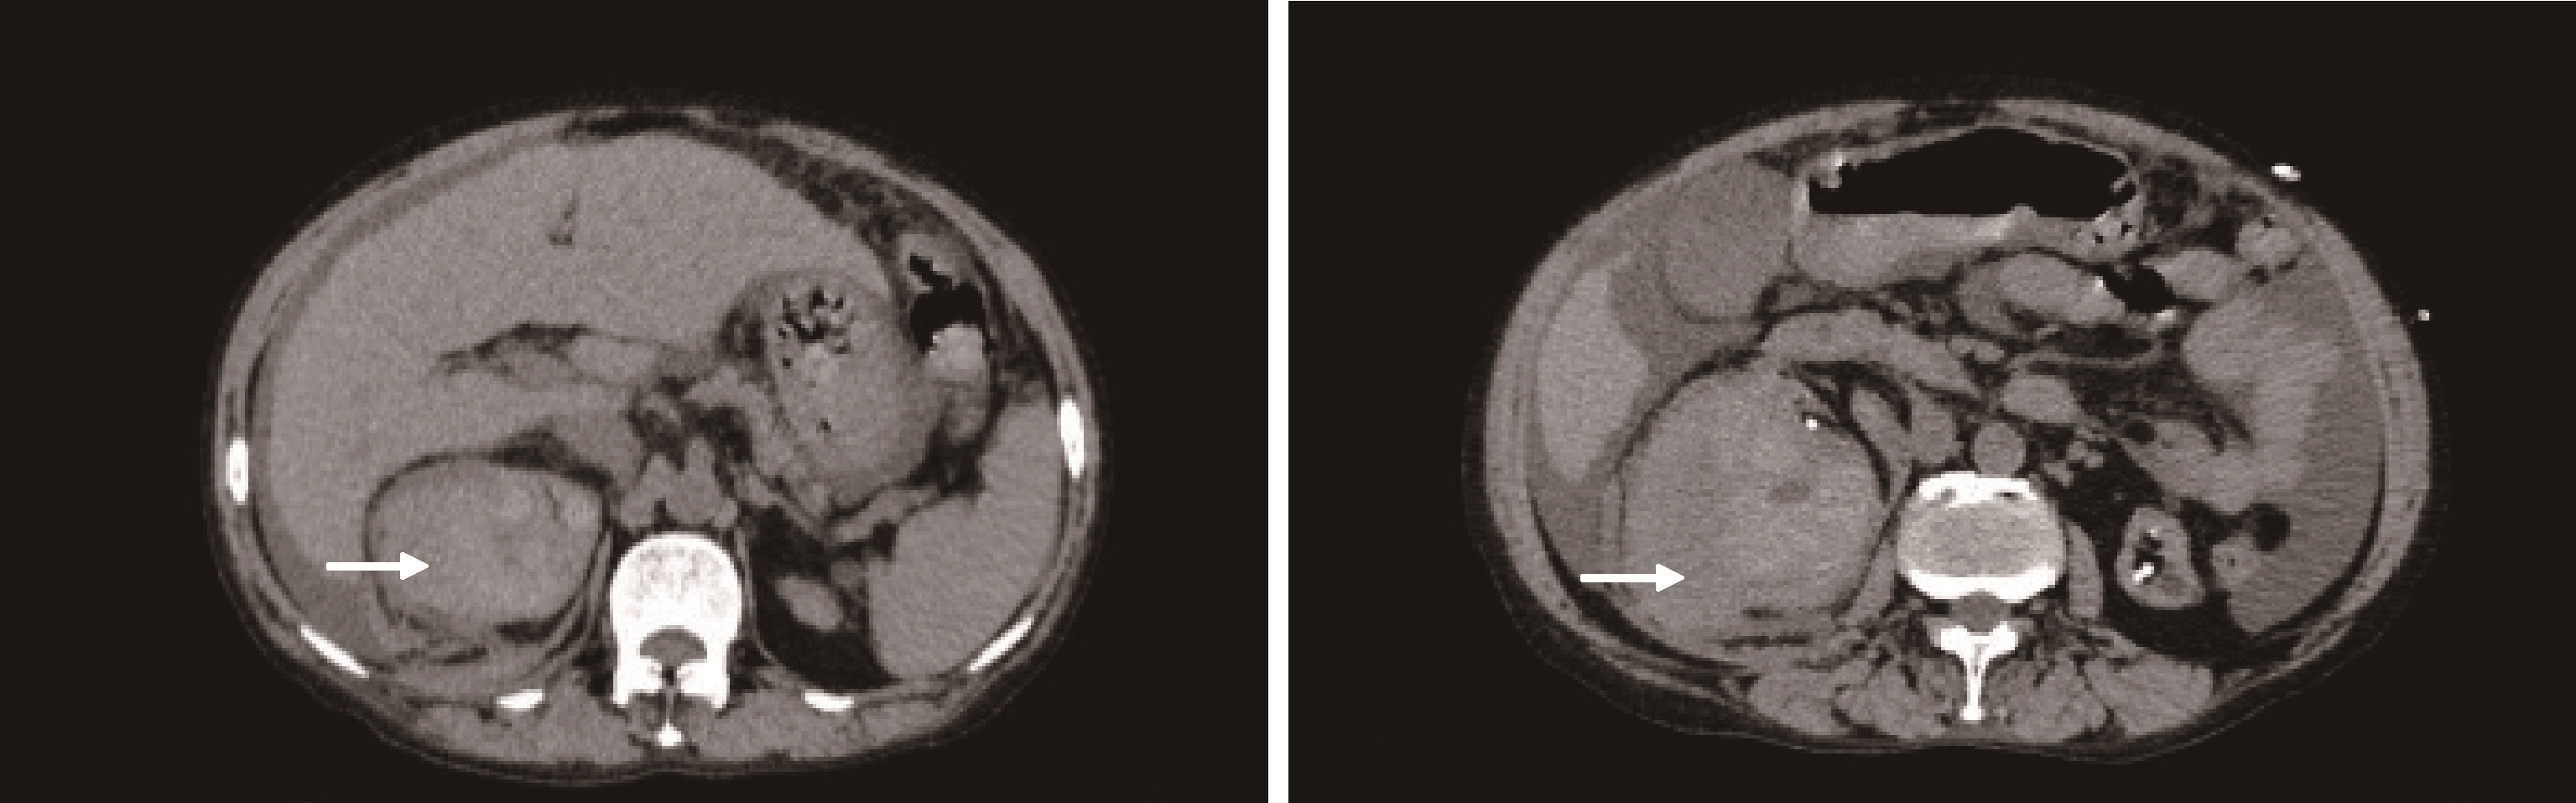

图1

病例1腹部CT图像"